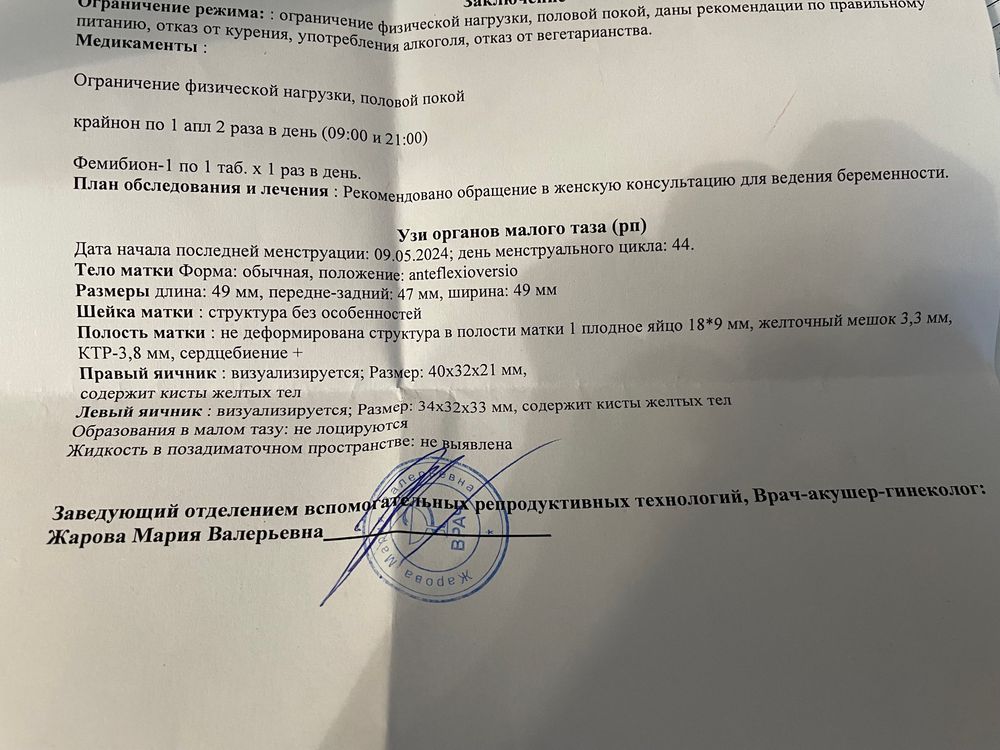

Девочки привет) сегодня 25 ДПП, на 18 дпп была на УЗИ, увидели ПЯ и ЖМ размером 2 мм, сегодня уже увидели эмбрион! Ре сказала все отлично и отпустила меня вставать на учет. Дала контакты гинеколога, 5 июля иду к ней на прием и встаю на учет😍 поверить до сих пор не могу, что я беременна!!!!